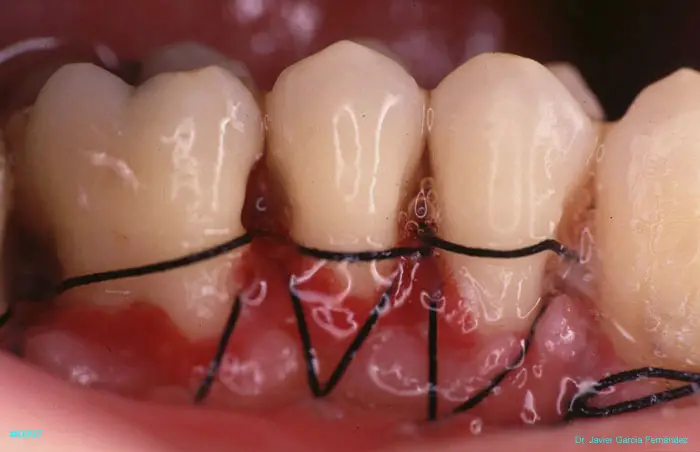

Atlas of Surgical Techniques in Periodontics. Chapter III. Atlas de Técnicas Quirúrgicas en Periodoncia